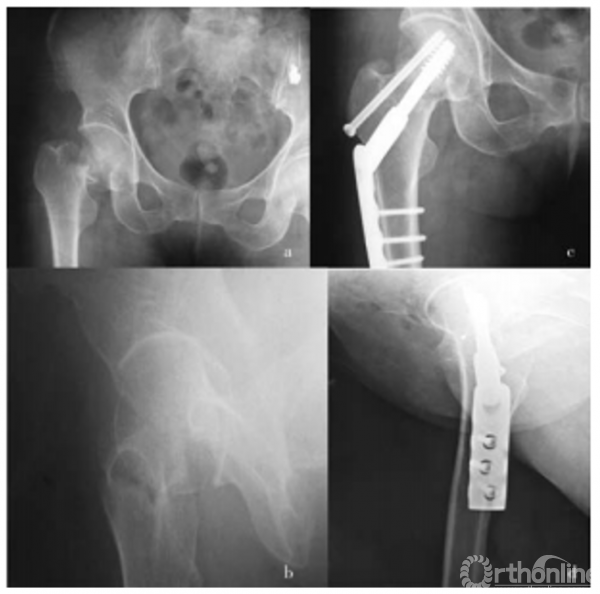

影像学资料

股骨颈骨折的再认识

病例分析

(滑动查看)